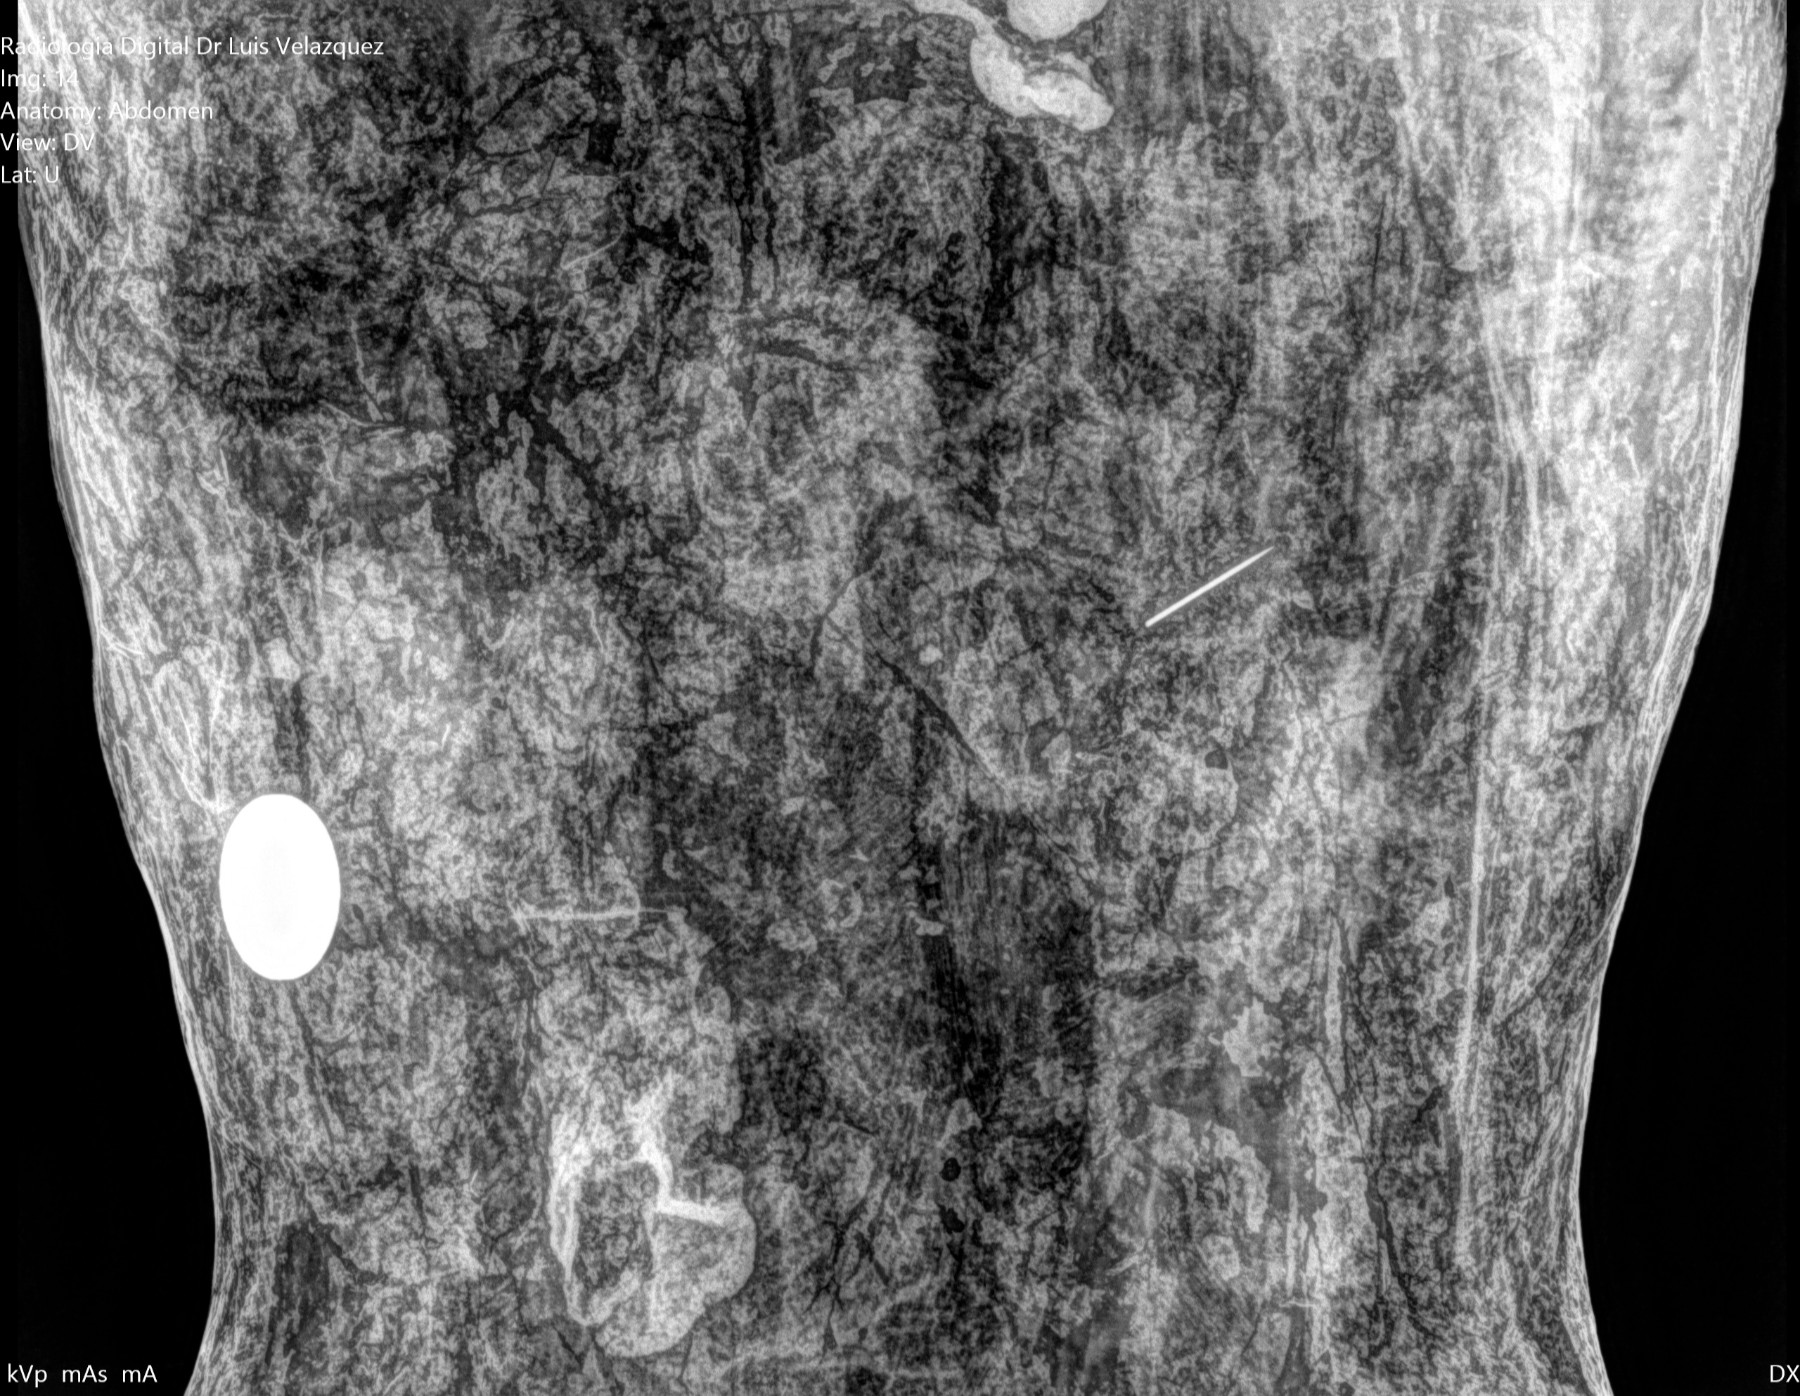

Radiología Digital como Herramienta Complementaria en el Dictamen de Bienes Muebles

Desde el descubrimiento de los rayos “X” y las placas radiográficas por Wilhelm Conrad Roentgen y su posterior difusión a través de la Asociación Físico médica de Wurzburg el 28 de diciembre de 1895, que fue la primera asociación que habló de los nuevos rayos que podían penetrar el cuerpo y fotografiar los huesos, ha habido muchos cambios tanto en la forma de obtener, procesar e incluso en la forma de visualizar, manejar y almacenar las placas radiográficas.